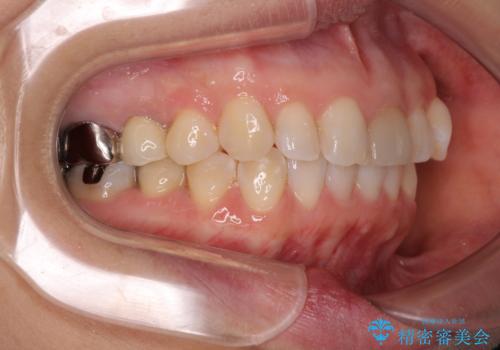

気になる下顎歯列のみをインビザラインで部分矯正

- 上下前歯のデコボコを気にして来院された患者様です。

カウンセリングにて詳しく話を聞いたところ、一番気になっているのは下顎前歯の叢生であり、上顎犬歯はあまり気になっていないとのことでした。

矯正治療は、歯の後戻りを抑制するために、治療終了後も保定装置をしっかりと使用していただくことが必須であるため、気になっている下顎だけを整えることで、その負担を半減できると考え、下顎のみの部分矯正として治療を行うこととしました。

装置としては、叢生の程度が強くなかったため、インビザラインの廉価版であるモデレート・パッケージを使用することとしました。

当院では治療前の歯列が整っていない限り、下顎前歯の舌側をワイヤーで固定するようにしています。下顎のみの部分矯正としたことで、マウスピース保定の負担を軽減することができました。

上顎は、失活して歯の色が変色しているため、将来的に補綴治療で自然な口元に仕上げていきたいとのことでした。